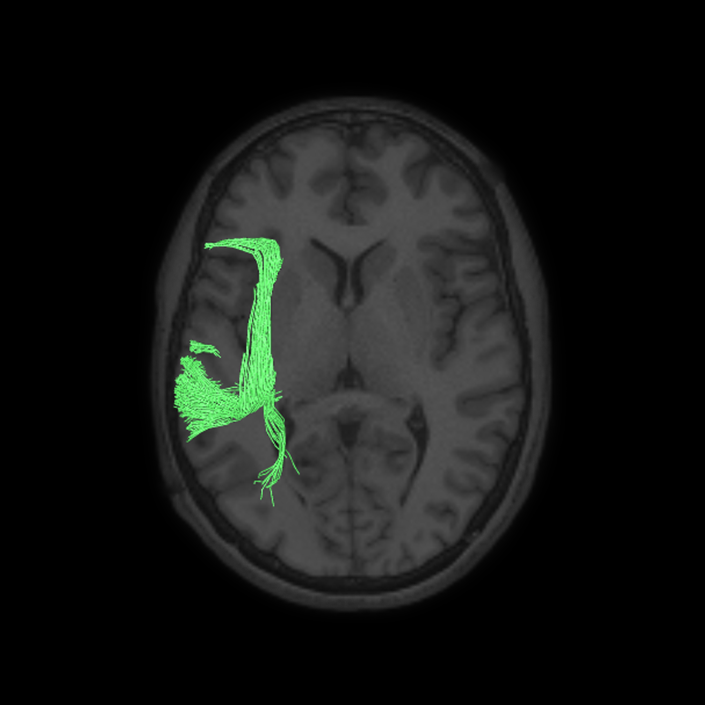

ᐅ SummaryArea 44: part of the inferior frontal gyrus of the lateral frontal lobe. Translates abstract and intentional information in the prefrontal cortex to more detailed representations to help guide the production of verbal and manual actions. In addition to its known association with Broca's area, is sometimes represented as part of Broca's complex ᐅ Where is it?Area 44 is at the posterior most part of the inferior frontal gyrus. It is the anterior bank of pars opercularis of the IFG. ᐅ What are its borders?Area 44 borders area 45 anteriorly and area 6r posteriorly. Area 8C is its medial border and its inferior border is wedged between then upper borders of Areas 6R and 6V. Its superior edge borders IFSp and IFJa. Its opercular surface is FOP4. ᐅ What are its functional connections?Area 44 demonstrates functional connectivity to areas SFL, IFSp, IFJa, 45, 47s, 47L, 9a, 9m, 8AV, 8BL and 8C in the dorsolateral frontal lobe, area 8BM in the medial frontal lobe, area 55b in the premotor areas, areas FOP5, AVI and PSL in the insula- opercular region, areas TGd, STSdp and STSvp in the temporal lobe, areas PFm, and PGi in the inferior parietal lobe, and no areas in the medial parietal lobe. ᐅ What are its white matter connections?Area 44 is structurally connected to the arcuate/SLF and the FAT. Connections with the arcuate/SLF project posteriorly and wrap around the Sylvian fissure to the middle temporal gyrus to end at TE1a and TE1m. There are also projections from the arcuate/SLF before it terminates to parcellations A5 and STSdp. The majority of the inferior connections of the frontal aslant tract end at 44, the tract is connected superiorly to superior frontal gyrus parcellations SFL, 6ma and s6-8. Local short association bundles are connected with 45 and 8C. White matter tracts from 44 in the right hemisphere have less consistent connections with the arcuate/SLF. ᐅ What is known about its function?Area 44 translates abstract and intentional information in the prefrontal cortex to more detailed representations to help guide the production of verbal and manual actions. Area 44, in addition to its known association with Broca's area, is sometimes represented as part of "Broca's complex", including Brodmann Areas 45, 46, 47 and the mesial supplementary motor area of 6, which contribute to a frontal-subcortical circuit. The right pars opercularis has also been implicated in cognitive inhibition in the overall context of working memory. |

DTI image |

ᐅ SummaryArea 45: part of the inferior frontal gyrus of the lateral frontal lobe. In addition to its known association with Broca's area, is sometimes represented as part of Broca's complex ᐅ Where is it?Area 45 is the lateral surface of pars triangularis of the IFG. ᐅ What are its borders?Area 45 borders area 47L anteriorly and area 44 posteriorly. Its superior edge borders area p47r, IFSa, and IFSp. Its opercular surface is conveniently named FOP5 ᐅ What are its functional connections?Area 45 demonstrates functional connectivity to areas SFL, IFSp, 44, a47r, 47s, 47L, 9a, 9p, 9m, 8AV, and 8BL in the dorsolateral frontal lobe, area 8BM in the medial frontal lobe, area 55b in the premotor areas, areas FOP5, and PSL in the insula-opercular region, areas TGd, TGv, TE1a, STSva, STSdp and STSvp in the temporal lobe, area PGi in the inferior parietal lobe, and area 31pd in the medial parietal lobe. ᐅ What are its white matter connections?Area 45 is structurally connected to the arcuate/SLF and IFOF. However, arcuate/SLF connections are not consistent across individuals. Connections with the arcuate/SLF project posteriorly and wrap around the Sylvian fissure to the middle temporal gyrus to end at TE1p. There are also projections from the arcuate/SLF before it terminates to parcellations A4 and PBelt. IFOF connections travel from 45 through the extreme/external capsule and continue posteriorly through the temporal lobe to end at occipital lobe parcellations V1, V2, V3 and V4. Local short association bundles connect with 44 and FOP4. ᐅ What is known about its function?Area 45, in addition to its known association with Broca's area, is sometimes represented as part of "Broca's complex", including Brodmann Areas 45, 46, 47 and the mesial supplementary motor area of 6, which contribute to a frontal-subcortical circuit. |

DTI image |

ᐅ SummaryArea 55b: part of the premotor areas. Relatively uncharacterized regions. In 1956, one of the only studies to characterize this regions concluded that the area played a role in language processing. ᐅ Where is it?Area 55b is located on the anterior half of the precental gyrus, approximately half way down its length along the convexity, just inferior to FEF. It also forms the adjacent floor of the precentral sulci and straddles slightly onto the posterior edge of the middle frontal gyrus. ᐅ What are its borders?Area 55b borders area FEF superiorly and PEF and area 6v inferiorly. Area 4 is its posterior border and areas 8AV and 8C form its anterior border across the precentral sulcus. ᐅ What are its functional connections?Area 55b demonstrates functional connectivity to area 4 in the motor strip, areas SCEF and SFL in the premotor areas, areas IFSp, IFJa, 8AV, 44, 45, and 47L in the lateral frontal lobe, areas STSda and STSdp in the temporal lobe, areas PSL and STV in the posterior opercular cortices, and area TPOJ1 in the lateral occipital lobe. ᐅ What are its white matter connections?Area 55b is structurally connected to the contralateral hemisphere and the superior longitudinal fasciculus. Contralateral connections course through the body of the corpus callosum to 6ma, 6a and 6mp. Connections with the superior longitudinal fasciculus connect 55b to parcellations PHT and PFm, and this tract terminates eventually in the temporal lobe at TGd. Local short association fibers connect with 8Av, 8C, IFJp, 3a, 3b and PEF. ᐅ What is known about its function?Area 55b is a relatively uncharacterized region. In 1956, one of the only studies to characterize this region concluded that the area played a role in language processing. |

DTI image |

ᐅ SummaryArea IFJa (inferior frontal junction, anterior): part of the lateral frontal lobe. Areas in the midventrolateral prefrontal cortex interact with posterior areas of the brain to retrieve specific auditory memories. The inferior frontal junction, in particular, serves as an important crossroads between bottom-up and top-down processing in the lateral prefrontal cortex. ᐅ Where is it?Area IFJA is located in the posterior portion of the inferior frontal sulcus. It comprises part of the inferior bank of the MFG in its upper portions. It is roughly superior to the pars opercularis portion of the inferior frontal gyrus. ᐅ What are its borders?Area IFJa borders area IFSp anteriorly and IFJp posteriorly. Its inferior border is area 44 and its superior border is area 8C. ᐅ What are its functional connections?Area IFJa demonstrates functional connectivity to areas 44, IFSa, IFSp, IFJp, and p9-46v in the dorsolateral frontal lobe, area SCEF in the medial frontal lobe, areas FEF, 55b PEF and 6r in the premotor areas, area FOP5 and PSL in the insular opercular regions, areas PH, PHT, and TE2p in the temporal lobe, areas MIP, TPOJ1, and LIPd in the inferior parietal lobe, and no areas in the medial parietal lobe. ᐅ What are its white matter connections?Area IFJa is structurally connected with the arcuate/SLF and surrounding parcellations. Connections with the arcuate/SLF project posteriorly and wrap around the Sylvian fissure to the middle and inferior temporal gyrus to end at TE1a, TE1m, and TE2a. There are also fibers that project superiorly form IFJa to end at SFL. These fibers are likely portions of the frontal aslant tract which has the majority of its inferior terminations at 44, a neighbor of IFJa. Local short association bundles connect to 8c, IFJa, IFSp, 44 and 8A. ᐅ What is known about its function?Areas in the midventrolateral PFC interact with posterior areas of the brain to retrieve specific auditory memories. The IFJ, in particular, serves as an important crossroads between bottom-up and top-down processing in the lateral prefrontal cortex. |

DTI image |

DTI image |

DTI image |

ᐅ SummaryArea SCEF (supplementary and cingulate eye field): part of medial superior frontal gyrus regions. Higher order oculomotor center implicated in appraising all possible oculomotor behaviors to direct primary oculomotor centers in goal- directed behavior. ᐅ Where is it?Area SCEF (supplementary and cingulate eye field) is located in the posterior medial SFG. ᐅ What are its borders?Area SCEF borders area 8BM anteriorly, areas 6ma and SFL superiorly, areas 6mp and 24dd posteriorly, and areas 24dv and p32pr inferiorly. ᐅ What are its functional connections?Area SCEF demonstrates functional connectivity to areas 1, 2, 3a, 3b in the sensory strip, area 4 in the motor strip, areas PEF, FEF, 55b, 6ma, 6mp, 6a, 6r, and 6v in the premotor regions, areas a24prime, p32prime, a32prime, 5mv, and 23c in the middle cingulate regions, areas IFJa, 46, and 9-46d in the lateral frontal lobe areas OP4, OP1, PFcm, 43, FOP1, FOP2, FOP3 FOP4, and FOP5 in the superior insula opercular regions, areas PSL, 52, A4, MI, PoI1 and PoI2 in the lower opercula and Heschl's gyrus regions, area PHT in the temporal lobe, areas AIP, MIP, VIP, LIPd, LIPv, PFop, PF, PFt, IP0, IPS1, 7AL, 7PL, and 7PC, in the lateral parietal lobe, areas 7am and DVT in the medial parietal lobe, area V1, V2, V3, V4 in the medial occipital lobe, areas V3a, V3b, V6, V6a, and V7 in the dorsal visual stream, area FFC of the ventral visual stream, and areas PH, TPOJ2, LO3, MST, and FST of the lateral occipital lobe. ᐅ What are its white matter connections?Area SCEF is structurally connected to the contralateral hemisphere and thalamus. Contralateral connections course through the body of the corpus callosum to end at SCEF, 8BL, SFL and 8BM. Thalamic projections travel through the ventral thalamus to the brainstem (Figure 32). Local short association bundles connect with SF, 8BM, SFL and 8BL. ᐅ What is known about its function?Area SCEF is a higher order oculomotor center implicated in appraising all possible oculomotor behaviors to direct primary oculomotor centers in goal-directed behavior. |

DTI image |

DTI image |

DTI image |

DTI image |

DTI image |

DTI image |

DTI image |

DTI image |

DTI image |